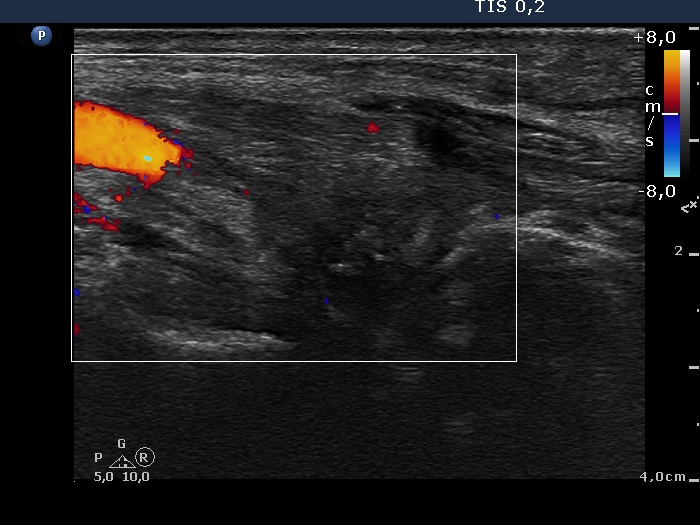

Five years after surgery (fourth row of images):

Clinical data: The patient had no complaints.

Palpation: no abnormality.

Functional test: TSH 1.16 mIU/L on daily 125 microgram levothyroxine.

Ultrasonography. There was minimaly if any thyroid remnant in the thyroid beds. Connective tissue replaced the thyroid.